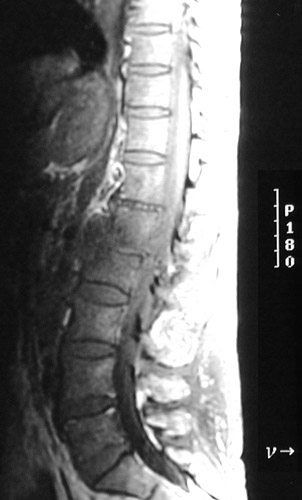

| The sagittal MRI scan view of the lumbar region of the spinal cord above demonstrates a fluid collection not as bright as the normal CSF with the T2 weighted scan, indicative of an epidural abscess. The infection has spread into the adjacent L1-L2 vertebral bodies. With the T1 weighted scan below can be seen the same epidural abscess. |